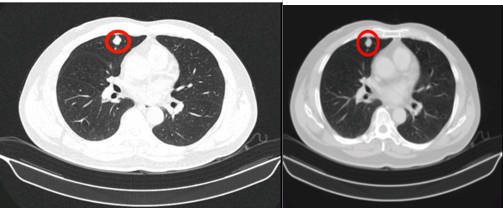

- Chụp CT lồng ngực:

Hình 1: Hình ảnh chụp CT ngực: có nốt đặc 13x11mm tại nhu mô ngoại vi phân thùy S3 phổi phải, bờ không đều, ngấm thuốc mạnh sau tiêm.